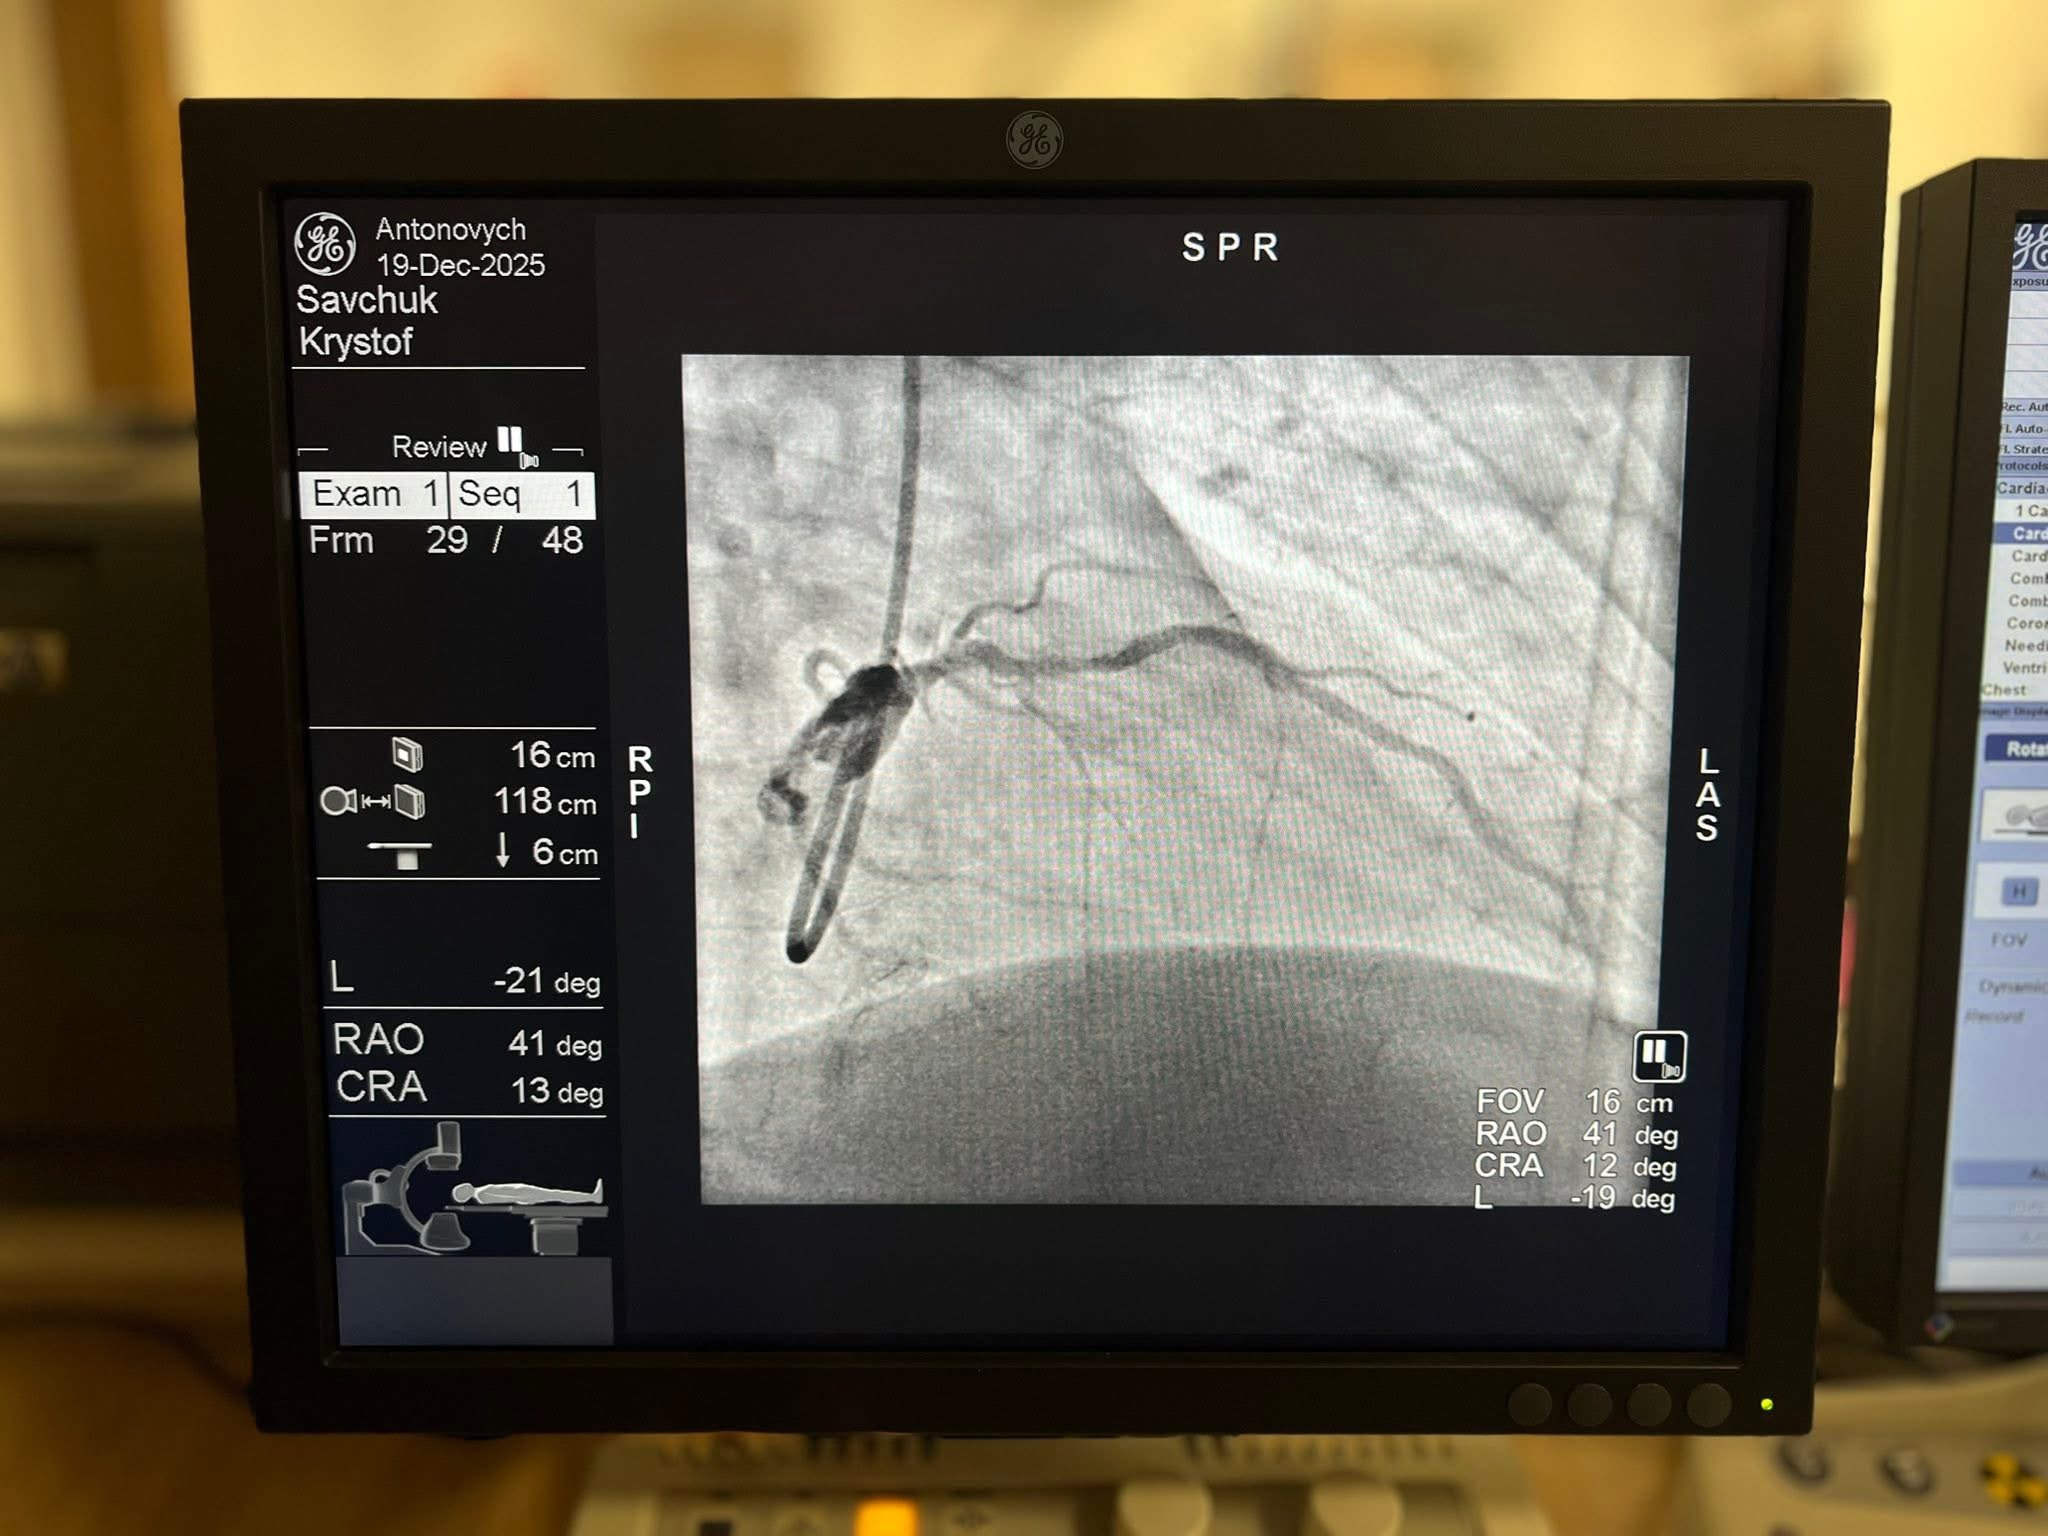

Кардіохірурги клініки серця та судин Університетської лікарні (кампус ім. Мар’яна Панчишина) відновили кровотік до серця 74-річному поляку без розрізу грудної клітки, застосувавши найсучаснішу методику. Таку операцію в Україні провели вдруге: перший раз операцію провели в Одесі, цього разу – у Львові.

Пацієнт Кшиштоф Савчук родом із Варшави та вже останні 10 років живе в Україні. Тут він одружився і переїхав у село на Львівщині. Усе життя чоловік працював інженером, а коли вийшов на пенсію, зайнявся вирощуванням помідорів і розведенням курей. Та його почало підводити серце. Чоловік переніс інфаркт, йому виконали стентування коронарних судин. Через атеросклероз вони забивалися наростами, які зменшують, а інколи повністю перекривають кровотік в судині серця. Інколи в них відкладається кальцій і вони стають твердими як камінь. Тож перше оперативне втручання дало короткотривалий результат: з часом чоловік почав втрачати рухливість, з’явилися задишка та знесилення. Він знову приїхав в університетську лікарню, де йому запропонували нестандартний метод лікування.

«Для пацієнтів із дуже вираженими кальцифікованими судинами, як у пацієнта, стандартні методики ангіопластики та стентування можуть бути малоефективними. Щоб уникнути ризиків, ми обрали інше найкраще рішення – орбітальну атеректомію», – каже керівник клініки серця і судин Дмитро Беш.

Орбітальна атеректомія викликає менше ускладнень і дозволяє ефективніше імплантувати стент. Через катетер у судину пацієнта лікарі вводять спеціальний високошвидкісний бур з алмазним напиленням. У судині він не просто крутиться, а описує коло (звідси й «орбітальна» в назві процедури). За допомогою цього інструмента лікарі сточують кальцій у судині на мікрочастинки.

Операція тривала годину, а вже за два дні пацієнт Кшиштоф повернувся додому.